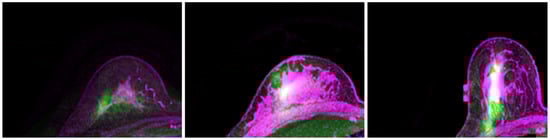

2.2. Modeling

2.2.2. Patient-Specific Biomechanical Model